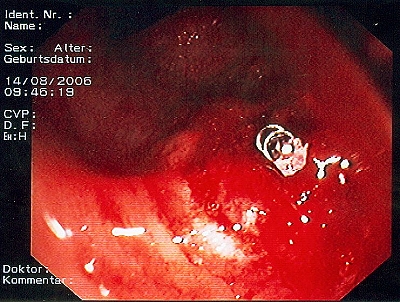

Gut sichtbarer Blutstrahl nach Abtragung eines Polypen

Sichere Blutstillung durch einen Metallclip